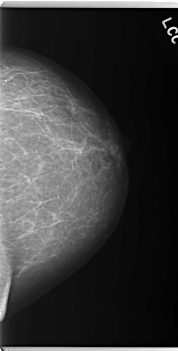

C_0159_1.LEFT_MLO

LEFT_CC LINES 5952 PIXELS_PER_LINE 3024 BITS_PER_PIXEL 12 RESOLUTION 50 NON_OVERLAY

LEFT_MLO LINES 5920 PIXELS_PER_LINE 2992 BITS_PER_PIXEL 12 RESOLUTION 50 NON_OVERLAY